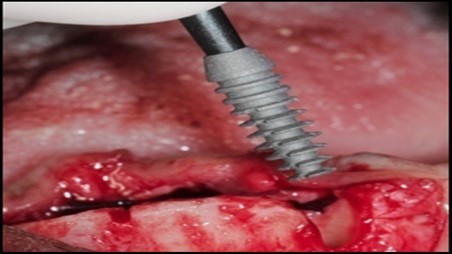

Under antibiotic prophylaxis and standard aseptic protocol, preparation of the patient was done by anaesthetizing the mandibular anterior segment with inferior alveolar nerve block using local anaesthesia of 2% lignocaine with 1:80,000 adrenaline. After the region was anaesthetized, full thickness crestal incision was made with surgical blade number 15 extending from first premolar on right side to first premolar on left side. The mucoperiosteal flap was elevated and bone was exposed. A pilot drill was introduced into the bone and two osteotomy sites were created using piezosurgery device without causing any damage to the adjacent anatomical structures. Two surgical implants (3.5x 11 mm) were inserted (Figure 3) using motor driver at 35 rpm and the landmark of reach was checked with profile gauge. After the implant seating tip has reached the adequate depth, cover screws are placed. Later flaps are approximated, suturing done using 3-0 vicryl suture material. Patient was prescribed with antibiotics and anti –inflammatory coverage. (Figure 4) Patient was recalled on the 7th day of surgery, suture removal was done.

Figure 3.Paralleling pins in each pilot osteotomy indicating their position

Figure 4.A 3.5mm x 11.0mm HA coated implant being inserted into the osteotomy in the area of the mandibular left canine